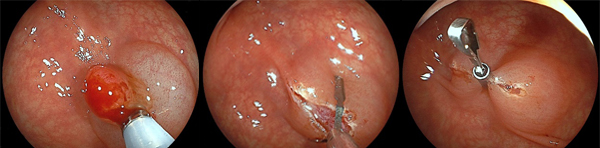

標準的なポリープ(7mm大)に対するEMR例

中:生理食塩水を粘膜下層(ポリープの下)に注入し、膨隆させます

右:スネア(輪っか)でポリープを絞扼します

中・右:クリップで切除後の創を縫縮します

この一連の流れにより、病変の診断と治療を同時に行うことができます。